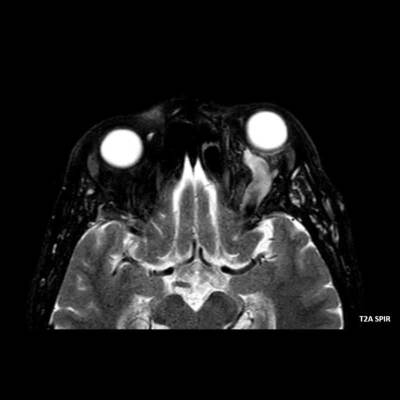

- A) Orbital MRG’de yağ baskılı T2A görüntülerde sol orbital globta ekzoftalmus (ok) izlenmiş olup retrobulbar yağlı dokuda kirlenmeler (ok) ve dilate superior oftalmik ven (ok) dikkati çekiyor. Beyin MRG’de kontrastlı T1A görüntüde sol kavernöz sinüste simetriğine oranla genişleme (ok) izleniyor.

- B) Pre ve post-kontrast yağ basklılı T1A görüntüler incelendiğinde superior oftalmik venin (oklar) kontrast madde verildikten sonra homojen dolum gösterdiği, dilate ve tortiyoze görünümde olduğu izleniyor.

- BT ve MRG: Propitozis, ekstraokuler kaslarda genişleme, superior oftalmik vende genişleme ve tortiyozite, ipsilateral kavernöz sinüste genişleme gösterilebilir. Serebral venöz konjesyonu olan ve intrakraniyal basınçları yükselen hastalarda serebral ödem, hemoraji, leptomeningeal ve kortikal venlerin dilastasyonunu görülebilir. Bunlara ek olarak travmaya sekonder olgularda BT ile eşlik eden fraktürler gösterilebilir.